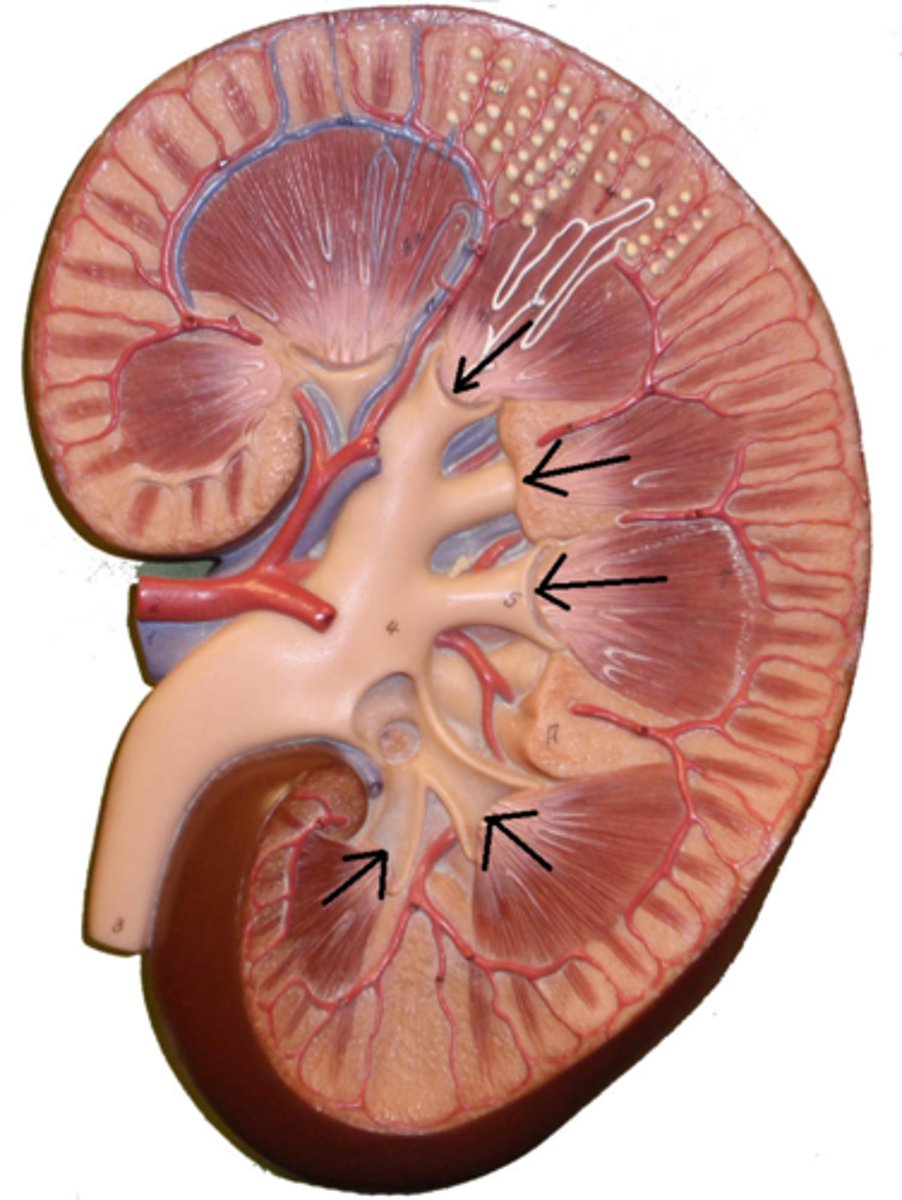

renal papilla

major calyx

minor calyx

renal pelvis

renal pyramids

ureter

renal columns